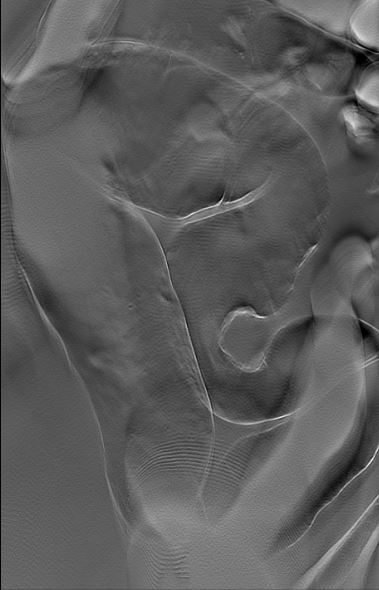

嚥下造影検査は、食べ物や飲み物を飲み込むときの動きを、X線透視装置を使ってリアルタイムに観察する検査です。バリウムを混ぜた飲み物や食べ物を実際に口から摂取していただき、その様子をテレビモニターで撮影しながら評価します。飲み込みの機能に問題がある場合その原因や程度を詳しく調べることができます。胃のバリウム検査は、造影剤と発泡剤(胃をふくらませる薬)を服用し、食道・胃・十二指腸の形や動き、粘膜の異常などをX線で詳しく調べる検査です。小腸造影検査は、造影剤を使って小腸の形や動き、異常の有無をX線で観察する検査です。小腸は、胃と大腸の間にある消化管で、全長約6〜7メートルもあり、通常のX線写真では観察が難しい部位です。

小腸造影 |